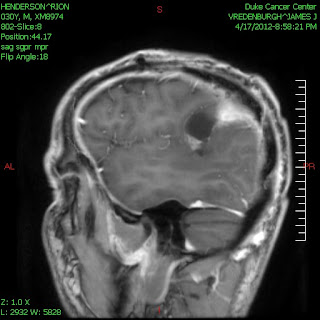

From this (November 2011):

To This (February 2012)

To this (April 2012)

And this (November 2011)

In a nut shell the 6 weeks of chemo and radiation was a success, Rion is healing still from surgery and almost all of the fluid that was present on his skull right after surgery has been reabsorbed. Since he did so well on the chemo/radiation regiment, the doctors are optimistic that the next round of chemo will go smoothly and we won't have to keep going back to Duke so frequently!! YAY

But even with all of this we know that we are blessed beyond measure. Comparing his new MRI (wow, can't believe that was just last week, it seems like so much longer) with the original diagnostic MRI from November reminds us that we were fortunate his tumor was operable and, through the work of God, we were about to get in touch with Duke and arguably the best neurosurgeon in the world. We've come across so many people that are living with inoperable brain tumors or whose surgery wasn't as successful as Rion's, these other brain tumor patients aren't as lucky as us and we always try to keep that in the front of our minds when something goes wrong. Our heart aches for each and every cancer patient who has it worse than us and at times we feel guilty complaining about side effects when it could be so very much worse. I couldn't imagine how horrible it would be if Rion still had to continue working right now, he can barely stay up for more than 5 or 6 hours these days and just doing house work leaves him worn out. I'm confident his treatment wouldn't be going as well if he had to manage the stress and demands of a job on top of his treatment & side effects. WE ARE BLESSED!